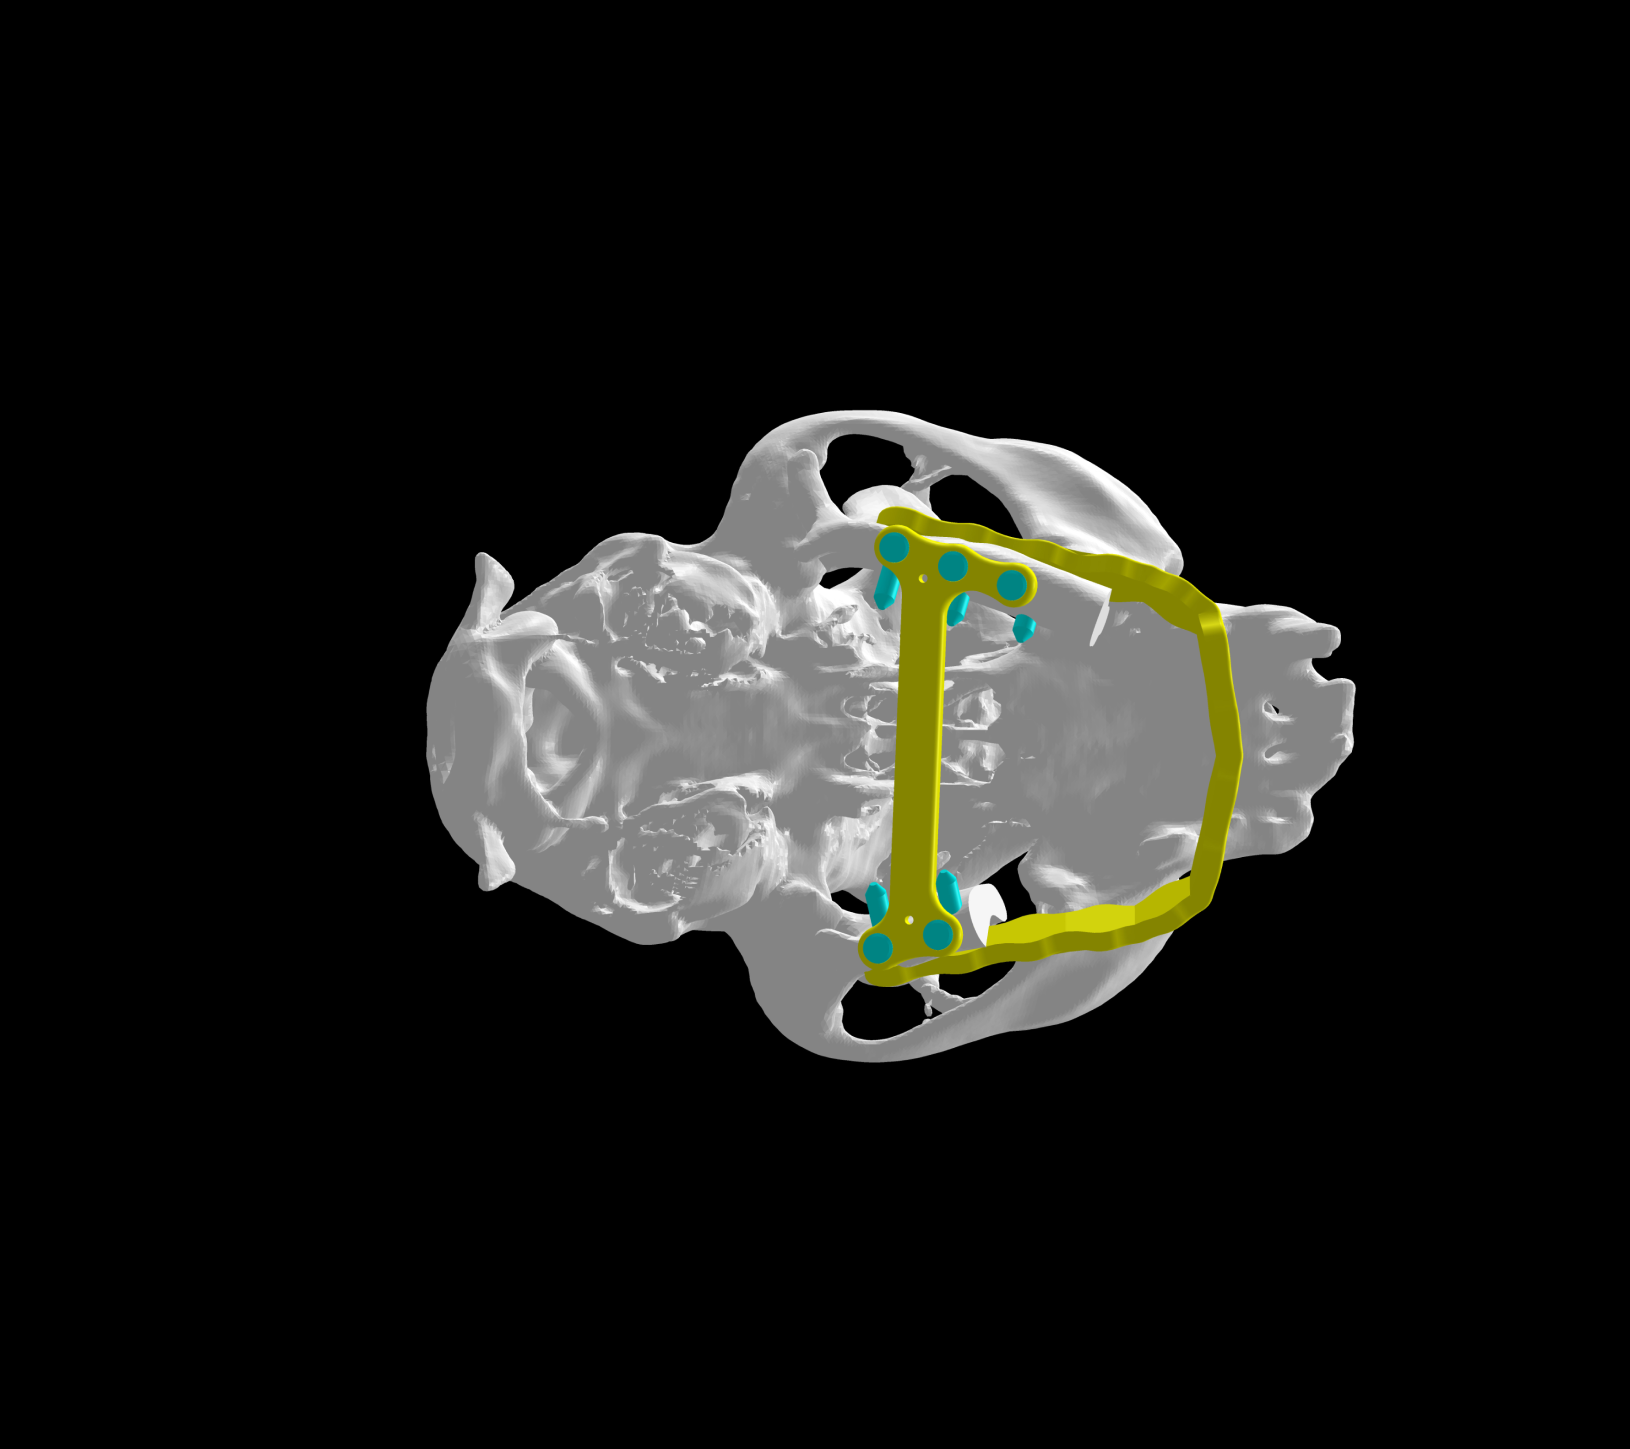

Esto se consigue gracias a los avances en la tecnología de fabricación, como la impresión 3D. Con esta tecnología se pueden crear implantes personalizados tanto en acero quirúrgico como en titanio a partir de imágenes médicas de tomografías computerizadas (TC) o resonancias magnéticas (RM).

Además disponemos la posibilidad de conseguir una fabricación rápida y de calidad de estos implantes gracias a trabajar de la mano con bioingenieros.